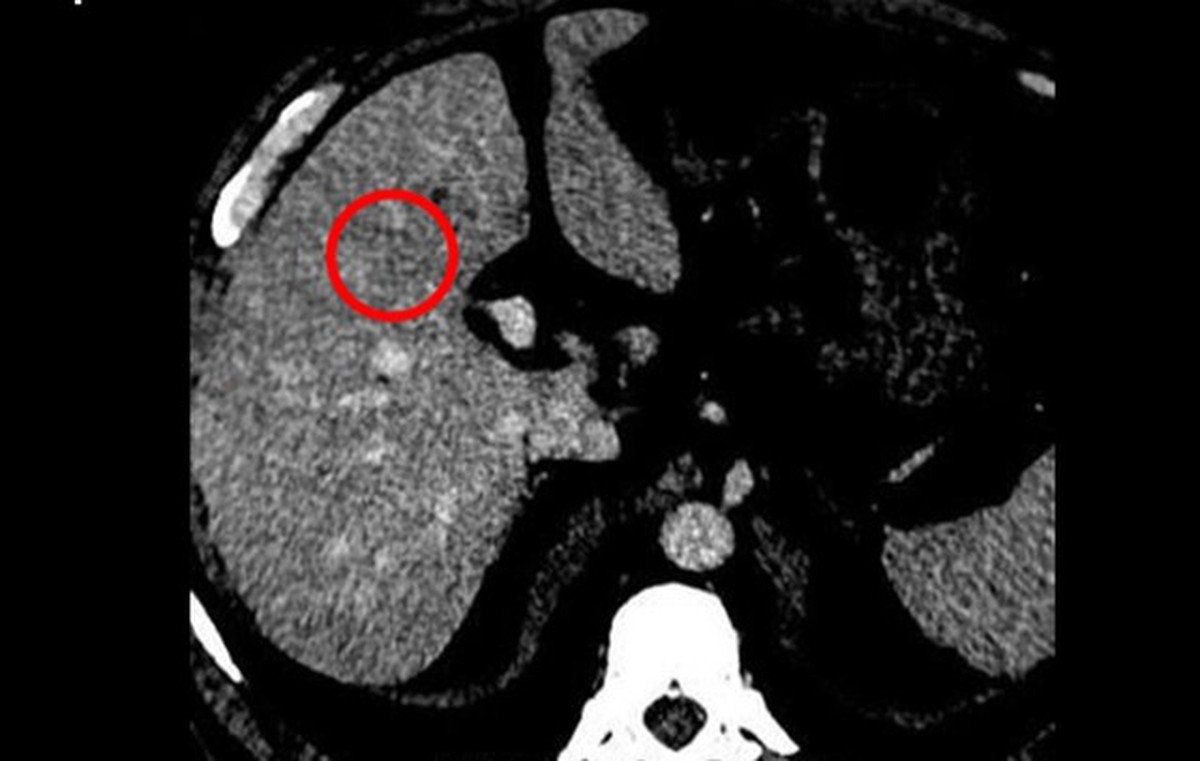

Tháng 1 năm nay, ông Từ (56 tuổi, sống tại thành phố Tuyền Châu, tỉnh Phúc Kiến, Trung Quốc) cùng vợ đi kiểm tra sức khỏe định kỳ tại bệnh viện địa phương. Kết quả nội soi dạ dày - thực quản khiến cả hai sốc nặng: cả hai đều được chẩn đoán mắc ung thư thực quản. May mắn là bệnh được phát hiện sớm, chưa có dấu hiệu di căn.

Sau khi đánh giá tình trạng bệnh, các bác sĩ đã chỉ định phẫu thuật nội soi trung thất để điều trị triệt căn ung thư thực quản cho cả hai bệnh nhân. Chỉ 5 ngày sau mổ, hai vợ chồng đã có thể xuất viện, sau khoảng một tuần phục hồi đã rút ống nuôi ăn và dần trở lại chế độ ăn bình thường.